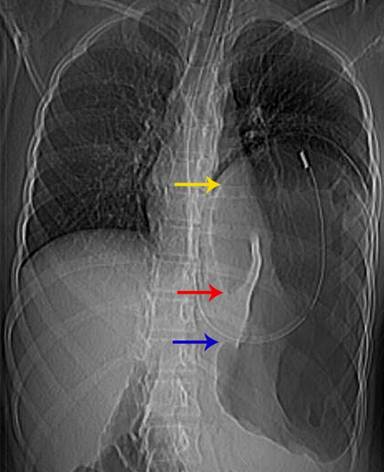

Laboratory investigations showed the patient to be anaemic (Hb 9 gm%) with leucocytosis (16,000/cubic mm) and a predominance of polymorphonuclear cells (80%). Scanogram revealed a dilated stomach with inverse orientation as evidenced by the position of the Ryle’s tube (Figure 1). A screening abdominal ultrasound failed to demonstrate the spleen in the left hypochondrium. The spleen was present in the umbilical region and extended into the left lumbar region. The bowel loops occupied the left upper quadrant. A contrast enhanced computed tomography (CECT scan) of the chest and abdomen was performed. It depicted a grossly distended stomach with the fundus lying in the left hemi-thorax and an air-fluid level within (Figure 2). The pylorus lay close but a little above the gastro-oesophageal junction, a finding consistent with gastric volvulus (Figure 3). There were no accompanying signs of gastric infarction. An enlarged spleen was visualised occupying the umbilical and the left lumbar region, extending along the undersurface of the left lobe of the liver and reaching below the lower pole of the left kidney (Figures 4, 5). The splenic pedicle had undergone torsion with consequent volvulus of pancreatic tissue. The splenic parenchyma however, had a homogenous attenuation, thus excluding any splenic ischemia. The pancreas was seen compressed between the stomach and the spleen (Figures 3, 5). A diagnosis of pancreatic volvulus due to torsion of wandering spleen, diaphragmatic hernia with an intra-thoracic gastric volvulus and resultant gastric outlet obstruction was thus established.

Figure 1. Scanogram reveals a markedly distended stomach (yellow arrow) with Ryle’s tube in situ. There is an inverse relation of the gastro-esophageal junction (blue arrow) and the pylorus (red arrow)- a finding consistent with intrathoracic gastric volvulus. |